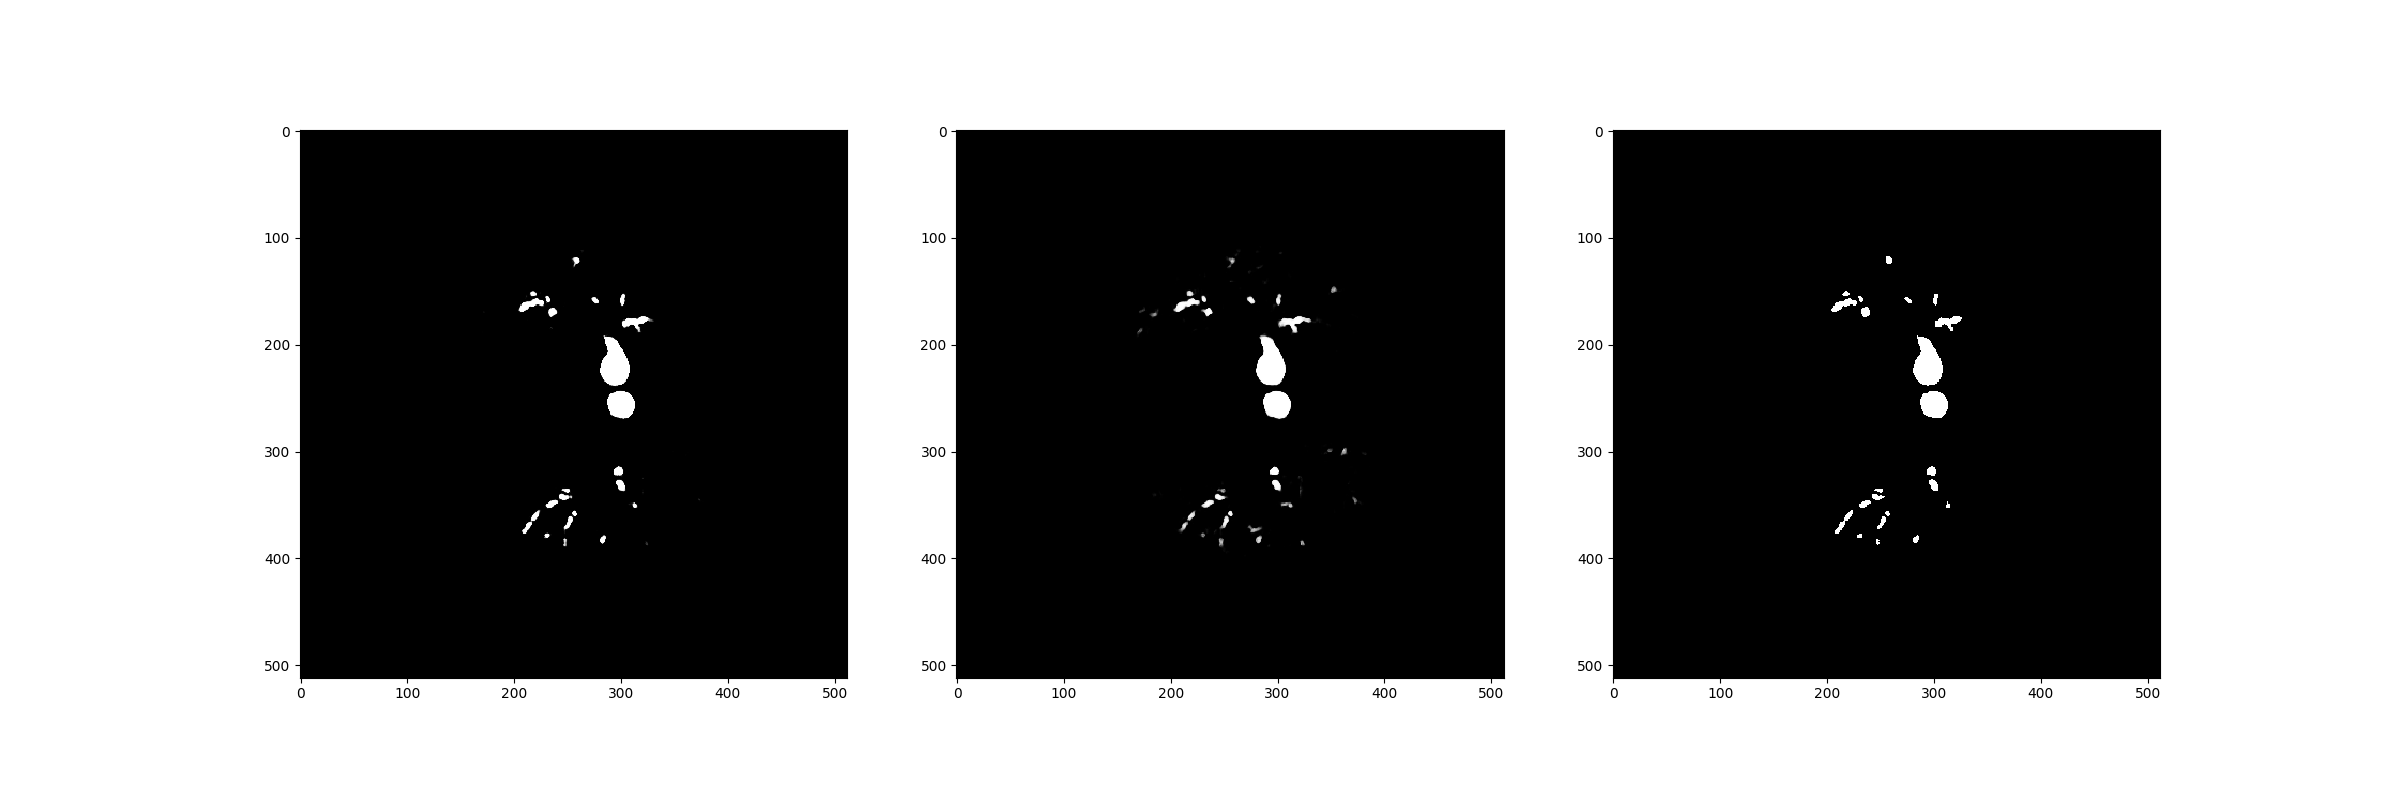

After the training process is completed, we compare the whole model performance with the CNN-only pretrained model in the test dataset.

Refer to caption

Figure 17: Comparison of prediction of the whole model, CNN pretrained model and ground truth: The left one is the predicted segmentation of the whole model, the middle one is the counterpart of the CNN pretrained model and the right one is the segmentation of the ground truth.

In the Figure 17, we can find out that there are tiny changes of the bronchi that are detected in the whole model, which are improved by the GNN module.